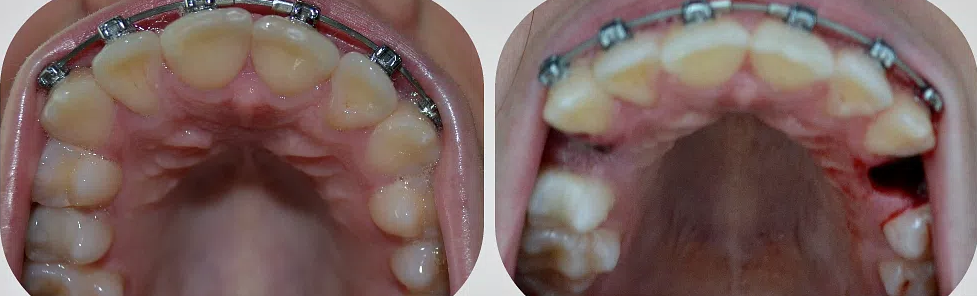

Удаление коренных зубов: фото до и после

В отдельных случаях настоять на удалении корневого зуба может и врач-ортодонт. Такое происходит, если требуется исправление прикуса, а пространства для подвижки зубов оказывается недостаточно.